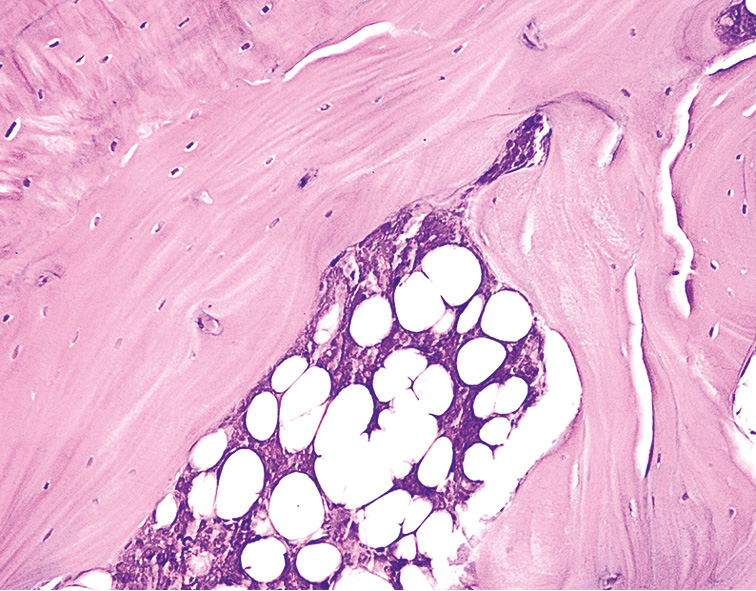

Микроскопические исследования СОП животных опытной группы через 2 мес от начала введения ДМГ показали, что в фрагментах изученной СОП среди клеток плоского эпителия определялись темноокрашенные железистоподобные структуры, а также хрящевая пластинка. Под пластами хрящевой ткани можно было визуализировать клеточно-волокнистую строму с большим количеством полигональных и вытянутых клеток с гиперхромными ядрами (рис. 2, 3).

Рис. 2. Слизистая оболочка пасти животного (опытная группа) через 2 мес от начала эксперимента. Окраска гематоксилином и эозином, ×120.

Fig. 2. The mucous membrane of the animal’s mouth (experimental group) 2 months after the start of the experiment. Staining with hematoxylin and eosin, ×120.

Рис. 3. Слизистая оболочка пасти животного (опытная группа) через 2 мес от начала эксперимента. Окраска гематоксилином и эозином, ×140.

Fig. 3. The mucous membrane of the animal’s mouth (experimental group). 2 months after the start of the experiment. Staining with hematoxylin and eosin, ×140.